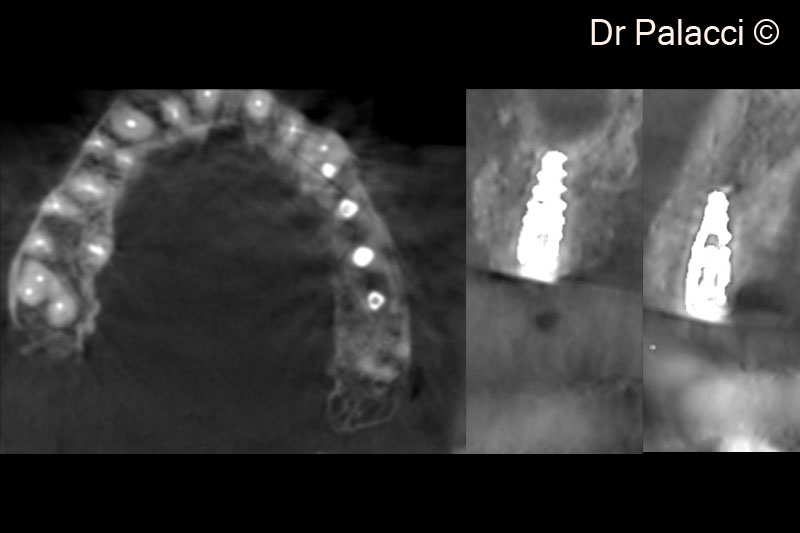

Hình ảnh X-Quang 3D cho thấy mất xương đáng kể quanh vùng chẽ chân răng 26,27,28. Vùng lõm rõ rệt ở răng số 24